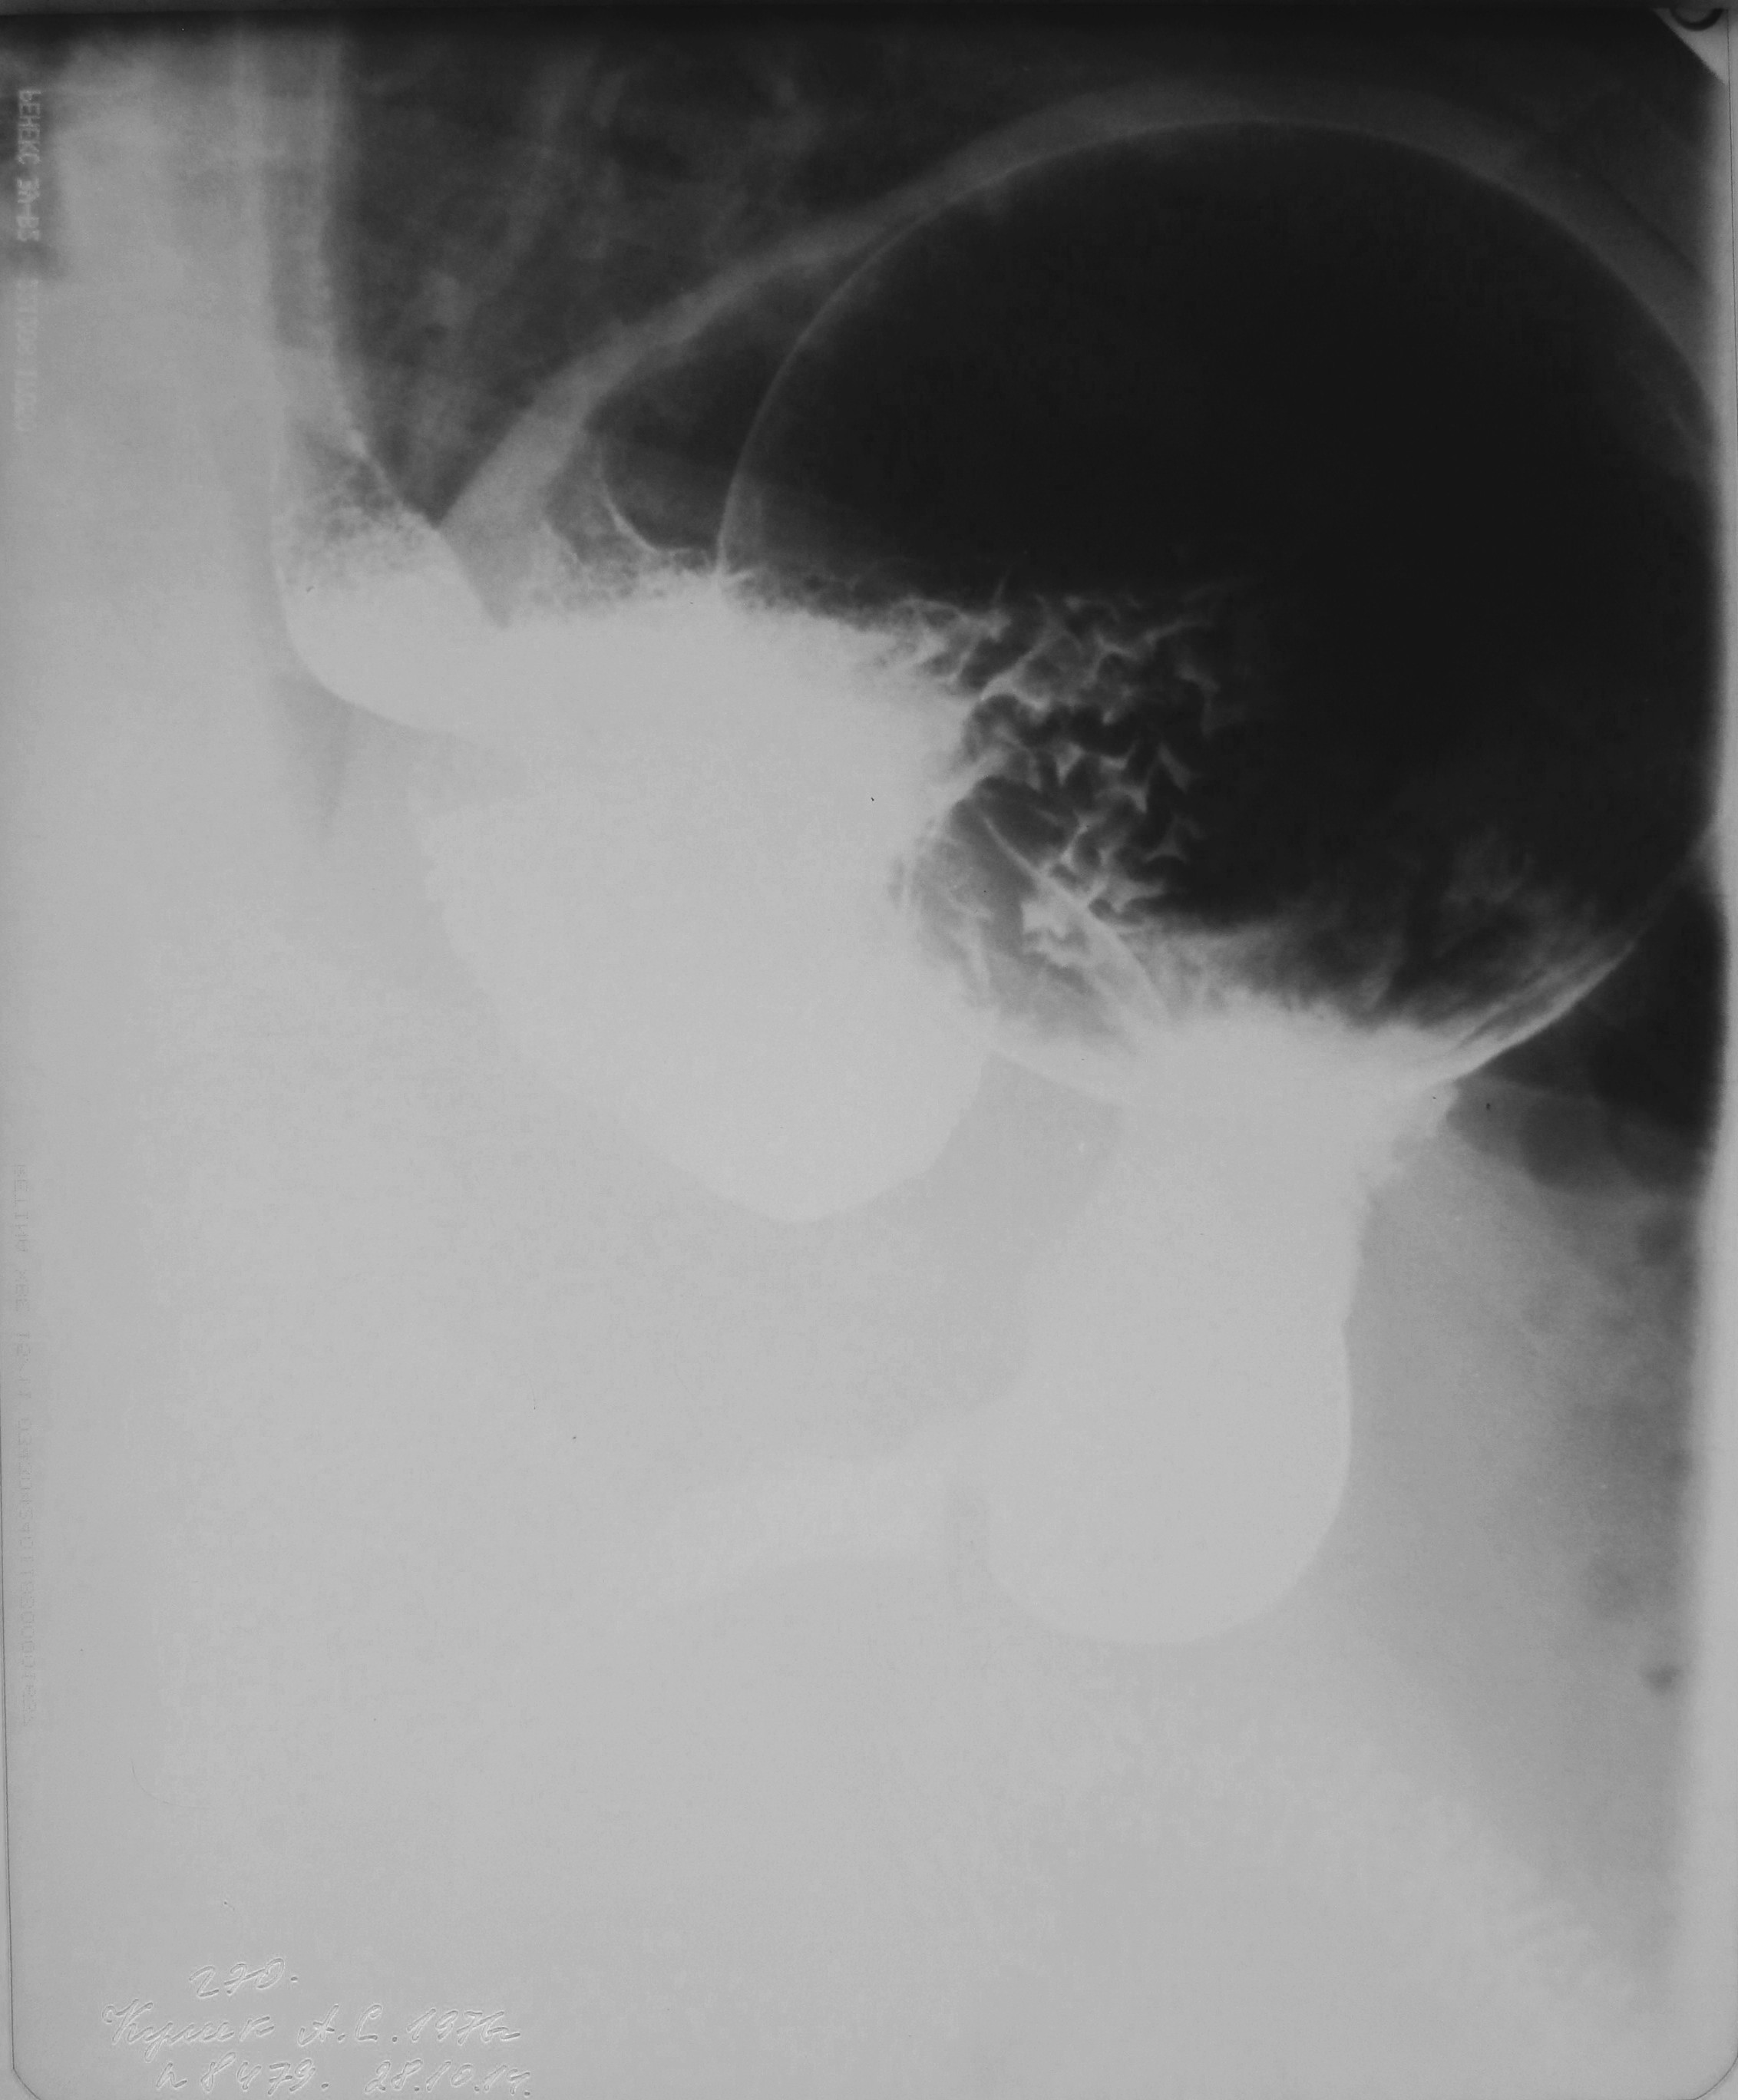

Сейчас погуглила - что-то есть в этом методе - проводится эндоскопически, по мере необходимости балло надувается/сдувается или убирается насовсем. Судя по размеру баллона у этого мужчины, ему еще худеть и худеть

Знаю два вида похудательных операций. Или бандаж, или когда открытым способом из желудка трубку делают,а это что-то странное.